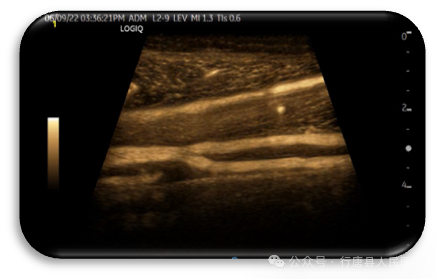

LOGIQ™E11全“芯”高端旗舰全身超声系统,创新的cSound™3.0™全“芯”成像平台,结合GE专利的冰晶探头、冰晶监视器为临床提供前所未有的优异成像性能。LOGIQ E11丰富先进的临床功能,可以在腹部、小器官、妇儿、心血管等多方面为临床医生提供有力的诊断依据,为老百姓的健康保驾护航。